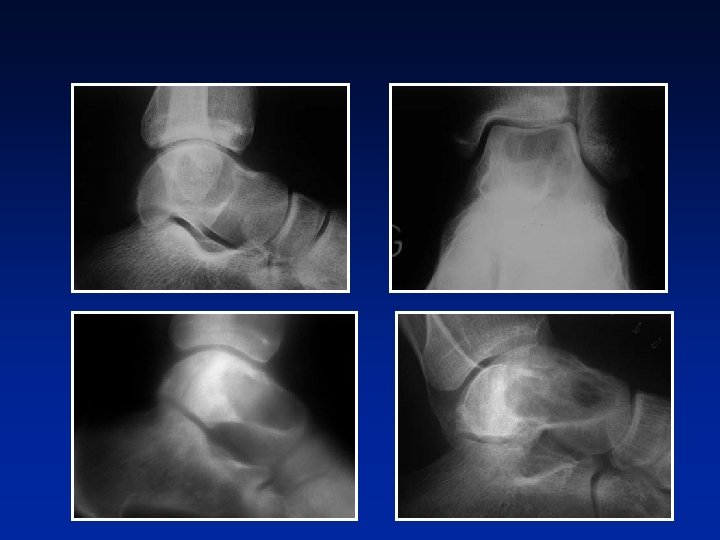

TUMOR DE CELULAS GIGANTES DIAGNOSTICO RADIOLOGICO Radiografía ¿pronóstico? (MÉARY)

TUMOR DE CELULAS GIGANTES DIAGNOSTICO RADIOLOGICO Radiología ¿pronóstico? (MÉARY) • Imagen clara osteolítica pura “tumor calmo” ♀ 18 a ♂ 30 a

TUMOR DE CELULAS GIGANTES DIAGNOSTICO RADIOLOGICO Radiología ¿pronóstico? (MÉARY) • Imagen clara osteolítica pura “tumor calmo” • Trabeculaciones inconstantes (nido de abejas)

TUMOR DE CELULAS GIGANTES DIAGNOSTICO RADIOLOGICO Radiología ¿pronóstico? (MÉARY) • Imagen clara osteolítica pura “tumor calmo” • • Trabeculaciones inconstantes (nido de abejas) En algunos casos, límites imprecisos “tumor activo”

TUMOR DE CELULAS GIGANTES DIAGNOSTICO RADIOLOGICO Radiología ¿pronóstico? (MÉARY) • Imagen clara osteolítica pura “tumor calmo” • Trabeculaciones inconstantes (nido de abejas) • En algunos casos, límites imprecisos “tumor activo” Destrucción cortical “tumores agresivos” ♂ 16 a

TUMOR DE CELULAS GIGANTES DIAGNOSTICO RADIOLOGICO Destrucción cortical “tumores agresivos” Importancia de la TAC o de la RMN